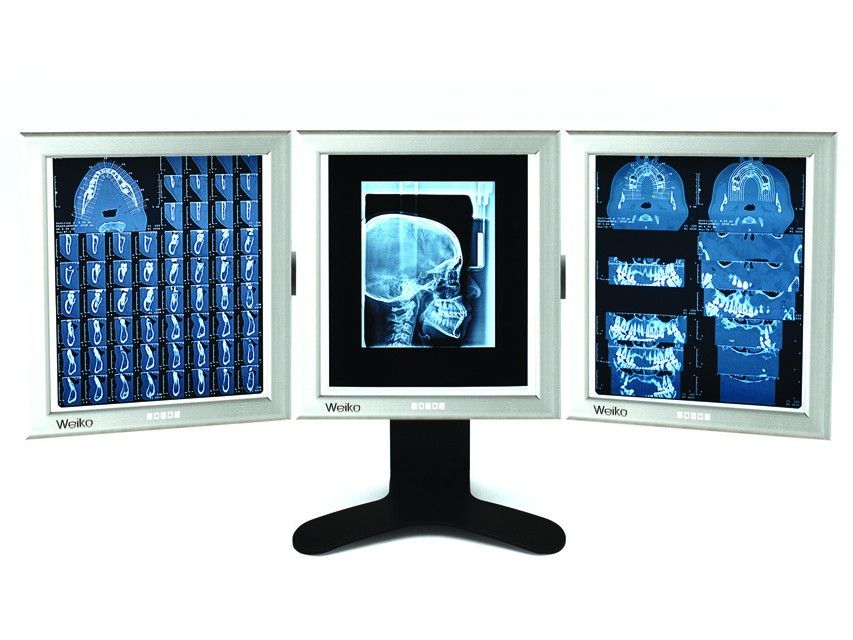

Negativoscopio Ultrapiatto Da Tavolo Led - 42 X 109 Cm (Triplo)